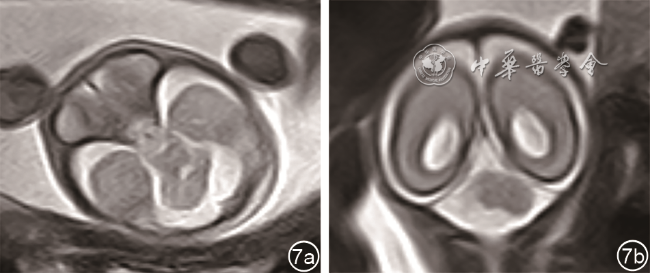

3. 磁共振辅助诊断4例,其中3例胎儿左侧小脑发育不全(图67),1例右侧小脑发育不全。

图6 孕25周胎儿(例5)产前颅脑轴位MRI T2WI 显示左侧小脑半球明显变小

图7 孕23周胎儿(例4)产前颅脑轴位MRI T2WI图像(图a);孕22周胎儿(例6)产前颅脑冠状位MRI T2WI图像(图b)均显示一侧小脑半球明显变小